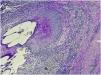

Piel. Formación continuada en dermatología Foliculitis en penacho del cuero cabelludo por Staphylococcus schleiferi

Foliculitis en penacho del cuero cabelludo por Staphylococcus schleiferi

Tufted folliculitis of the scalp caused by Staphylococcus schleiferi